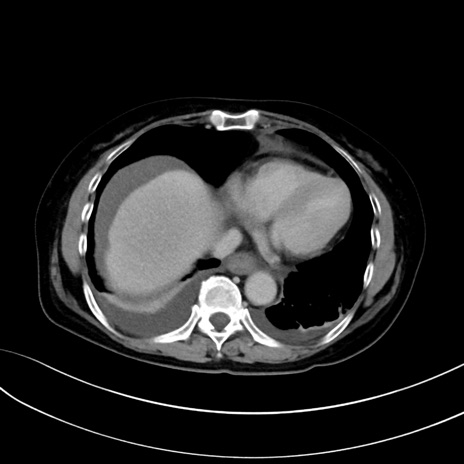

症例13 CT(横断像)1日半後